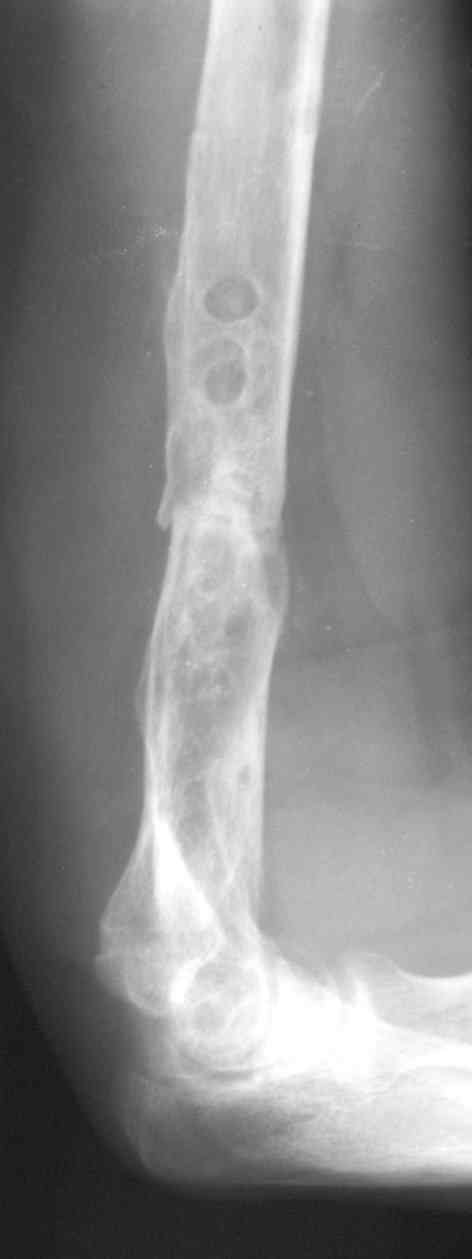

Рентгеновская версия реконструкции. хронология:

после операции, 2 мес. после операции, через 1 год

Движения в полном объеме восстановлены к 2 мес. после операции. Если надо могу показать мультик. Сейчас уже прошло более 3 лет, больная не

показывается. Успехов ЛАФ.